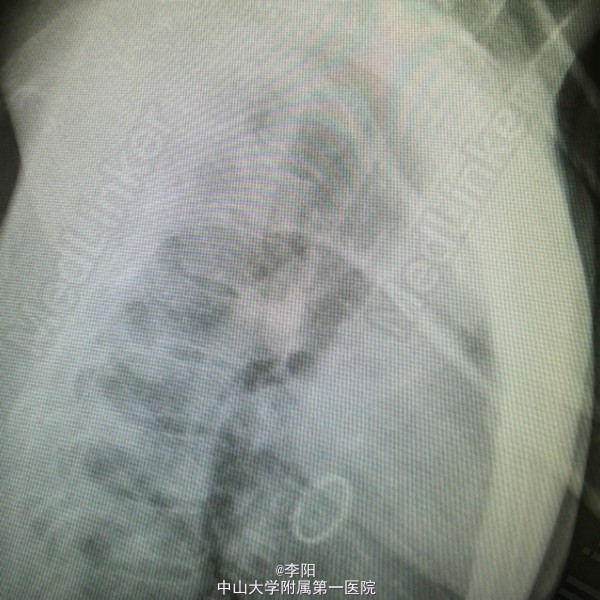

风湿性心脏病一例

风湿性心脏病

患者5年前出现劳动后乏力,气促,休息后好转,无胸痛,咳嗽,咳痰,无端坐呼吸,无颜面及下肢浮肿,当地医院就诊心脏彩超示:风湿性心脏病,我院彩超提示:风湿性心脏病,二尖瓣狭窄并关闭不全